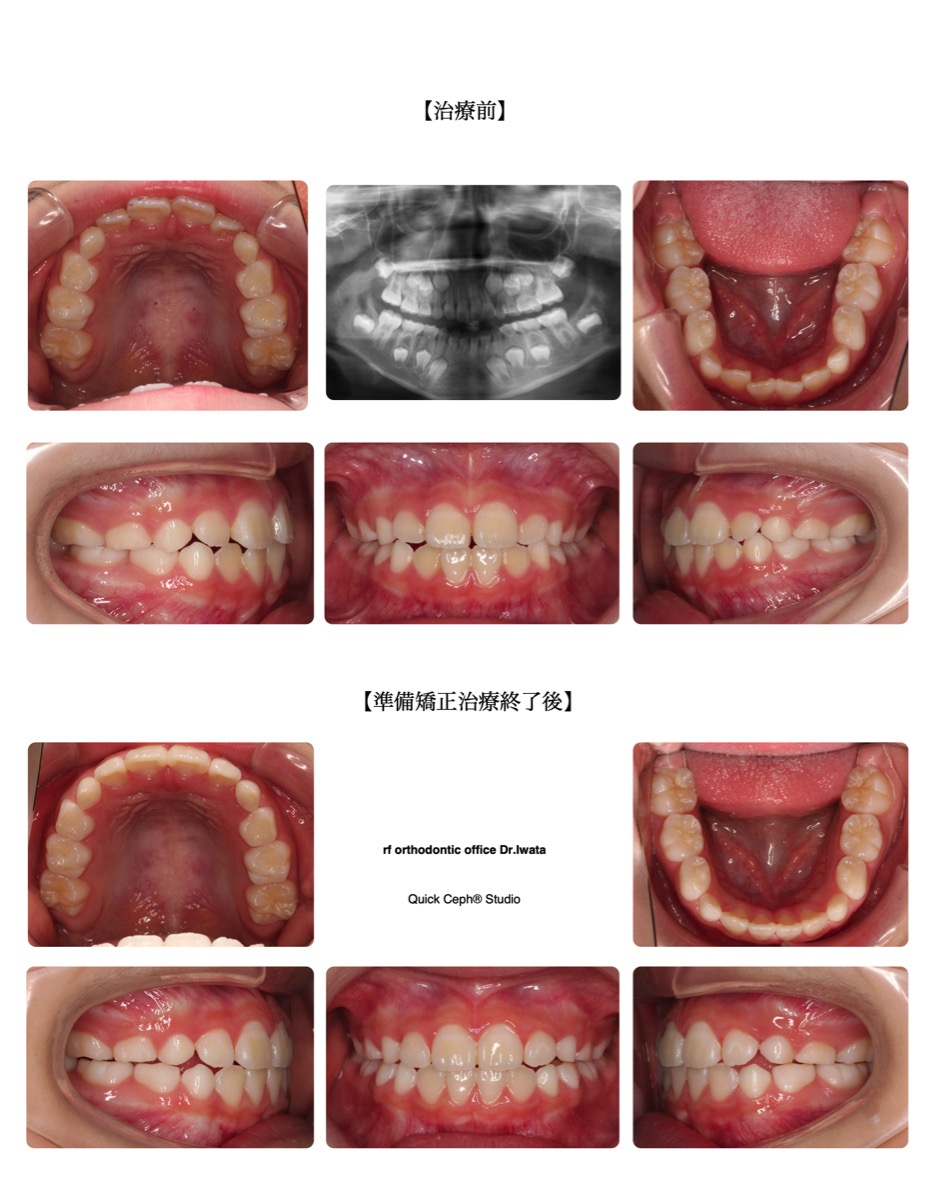

反対咬合症例 <重度叢生を伴う反対咬合に対する抜歯矯正治療>

【主訴】上下のガタガタがひどくて食事や歯磨きがしづらい。見た目も気になる。前歯も受け口になっていて口元も良く…